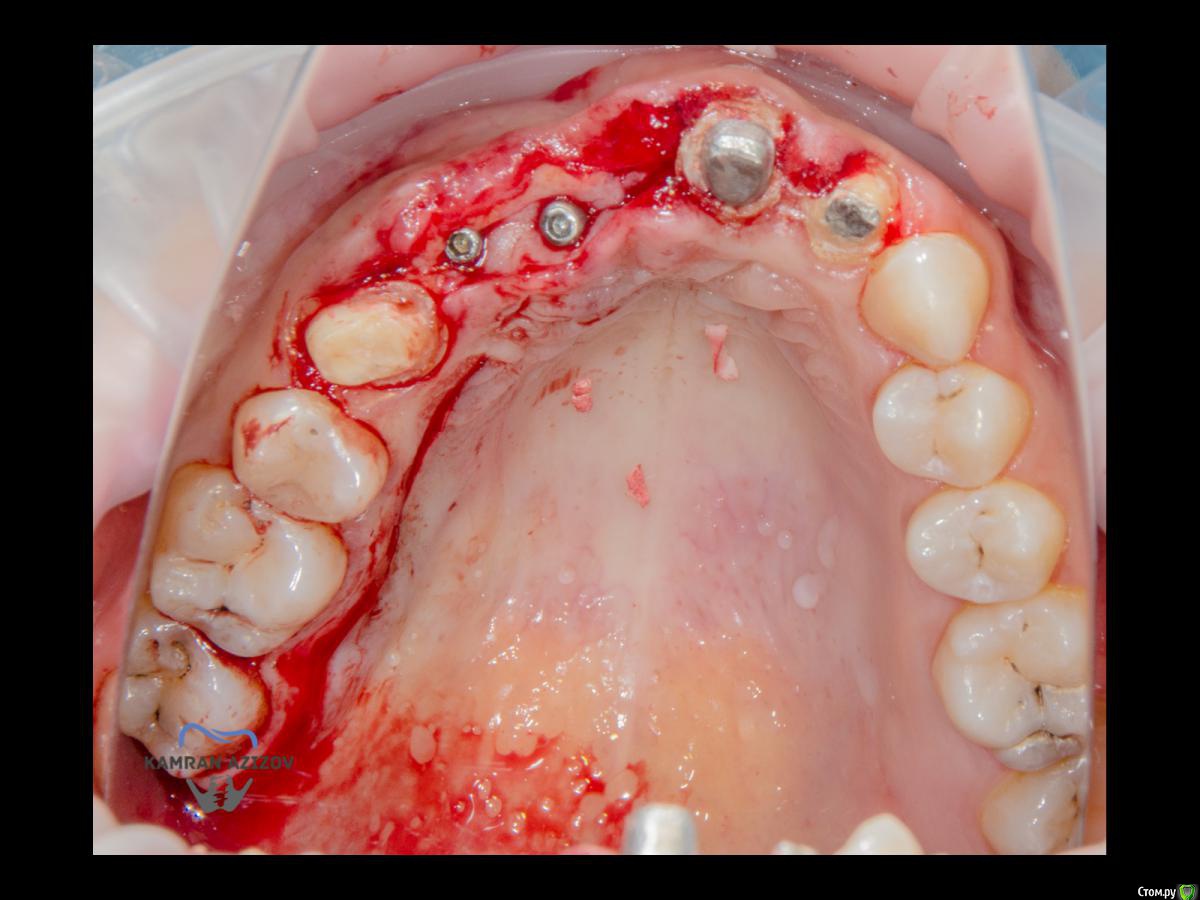

kamranchick Опубликовано 6 апреля, 2019 Поделиться Опубликовано 6 апреля, 2019 (изменено) Хай Гайсдавно ничего не комментировал и не выкладывал, что то настроения не было, да и муза не посещалаСитуация следующаяпришла пациентка, жалобы на неприятный запах из рта, сначала не понял что за хрень, ну как распилил мост понял че к чему... халтура.Ну и по кейсуУдаление клыка и 2ки, через 2 месяца навигация, имплантация + Шашлыки по карлоссу, смена формиков, временное протезирование. только мягкие ткани, Изменено 6 апреля, 2019 пользователем kamranchick 7 1 Ссылка на комментарий

Nazim_NV86 Опубликовано 7 апреля, 2019 Поделиться Опубликовано 7 апреля, 2019 Пятый Без пина шаблон не держался? Ссылка на комментарий

kamranchick Опубликовано 8 апреля, 2019 Автор Поделиться Опубликовано 8 апреля, 2019 Пятый Без пина шаблон не держался? держался) но сделали на всякий случай) Ссылка на комментарий